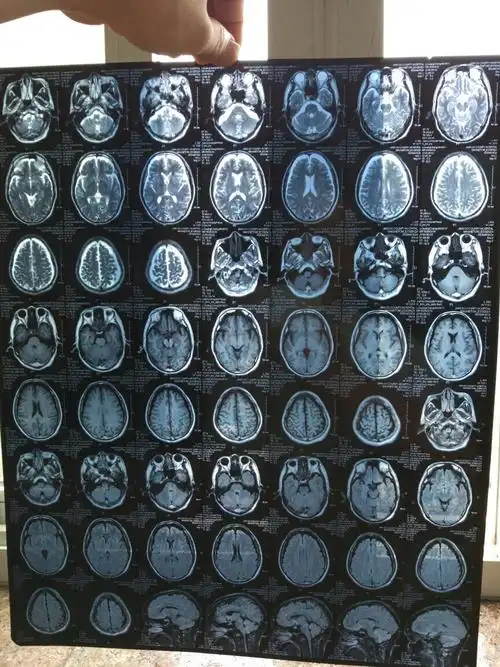

体检发现头颅ct局限脑萎缩

【随想】这个年轻人真的脑萎缩了?